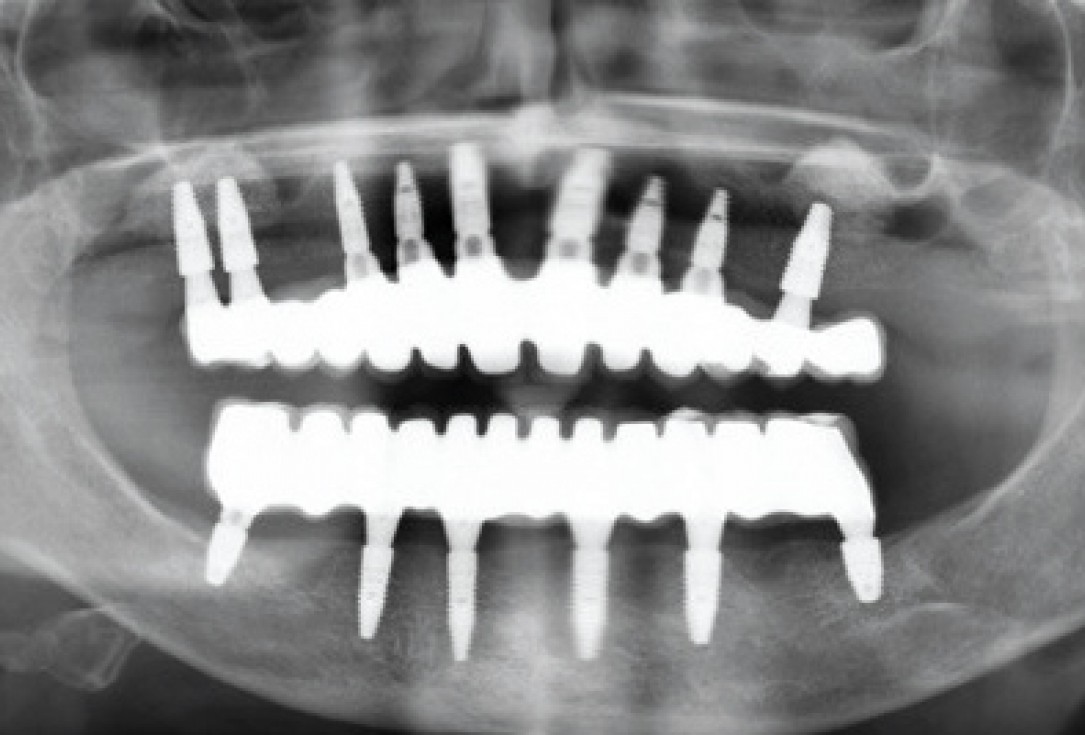

01/11 - Pre-operative OPG of the patient

Sinus lift with maxresorb® inject - Dr. E. Valdimarsson